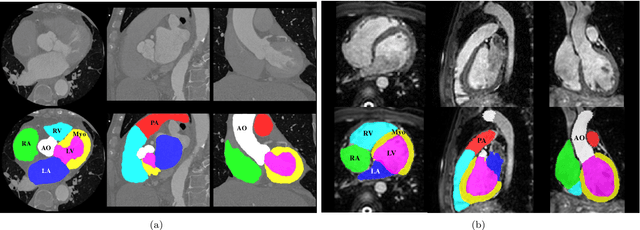

Abstract:Knowledge of whole heart anatomy is a prerequisite for many clinical applications. Whole heart segmentation (WHS), which delineates substructures of the heart, can be very valuable for modeling and analysis of the anatomy and functions of the heart. However, automating this segmentation can be arduous due to the large variation of the heart shape, and different image qualities of the clinical data. To achieve this goal, a set of training data is generally needed for constructing priors or for training. In addition, it is difficult to perform comparisons between different methods, largely due to differences in the datasets and evaluation metrics used. This manuscript presents the methodologies and evaluation results for the WHS algorithms selected from the submissions to the Multi-Modality Whole Heart Segmentation (MM-WHS) challenge, in conjunction with MICCAI 2017. The challenge provides 120 three-dimensional cardiac images covering the whole heart, including 60 CT and 60 MRI volumes, all acquired in clinical environments with manual delineation. Ten algorithms for CT data and eleven algorithms for MRI data, submitted from twelve groups, have been evaluated. The results show that many of the deep learning (DL) based methods achieved high accuracy, even though the number of training datasets was limited. A number of them also reported poor results in the blinded evaluation, probably due to overfitting in their training. The conventional algorithms, mainly based on multi-atlas segmentation, demonstrated robust and stable performance, even though the accuracy is not as good as the best DL method in CT segmentation. The challenge, including the provision of the annotated training data and the blinded evaluation for submitted algorithms on the test data, continues as an ongoing benchmarking resource via its homepage (\url{www.sdspeople.fudan.edu.cn/zhuangxiahai/0/mmwhs/}).